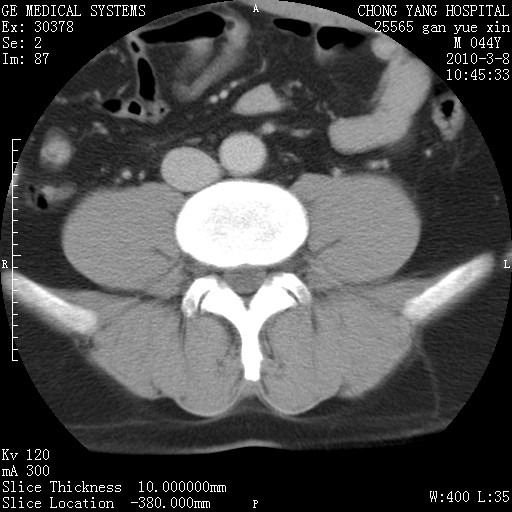

标题: CT24940:主动脉增强,典型病例。 [打印本页]

标题: CT24940:主动脉增强,典型病例。

夹层动脉瘤。

动脉夹层

夹层动脉瘤,典型

主动脉夹层。

动脉夹层的分型:

⒈debakey分型:根据主动脉夹层累及部位,分为三型:ⅰ型:原发破口位于升主动脉或主动脉弓部,夹层累及升主动脉、主动脉弓部、胸主动脉、腹主动脉大部或全部,少数可累及髂动脉。ⅱ型:原发破口位于升主动脉,夹层累及升主动脉,少数可累及部分主动脉弓。ⅲ型:原发破口位于左锁骨下动脉开口远端,根据夹层累及范围又分为ⅲa,ⅲb。ⅲa型:夹层累及胸主动脉。ⅲb型:夹层累及升主动脉、腹主动脉大部或全部。少数可累及髂动脉。

⒉stanford分型:a型:夹层累及升主动脉,无论远端范围如何。b型:夹层累及左锁骨下动脉开口以远的降主动脉。

夹层动脉瘤,少量胸水

夹层动脉瘤;左侧少量胸腔积液。

典型主动脉夹层。